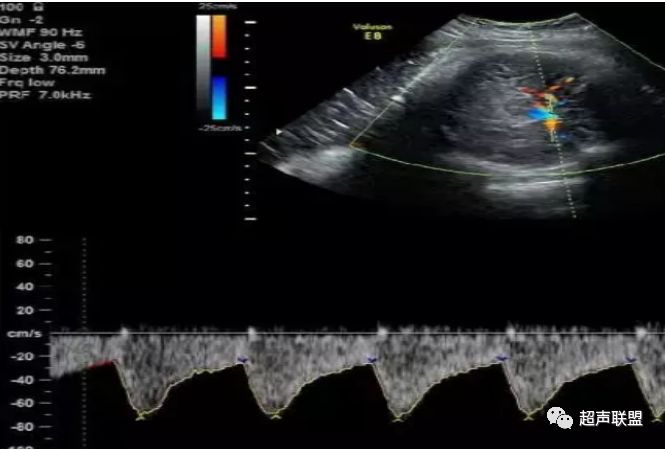

图3 正常大脑中动脉血流频谱

图4 大脑中动脉血流阻力减低